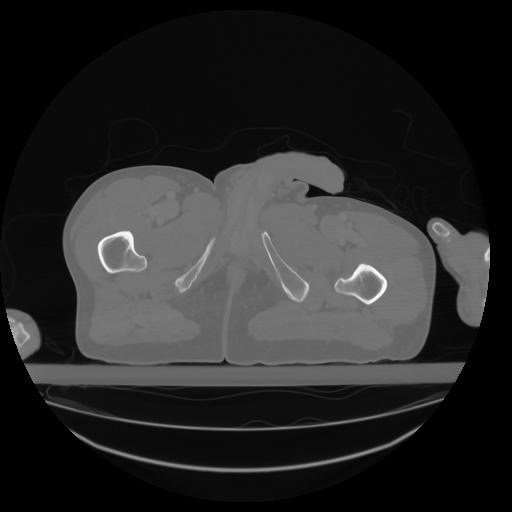

27 CUERPO,CE,Axial,3.0,CUERPO,,